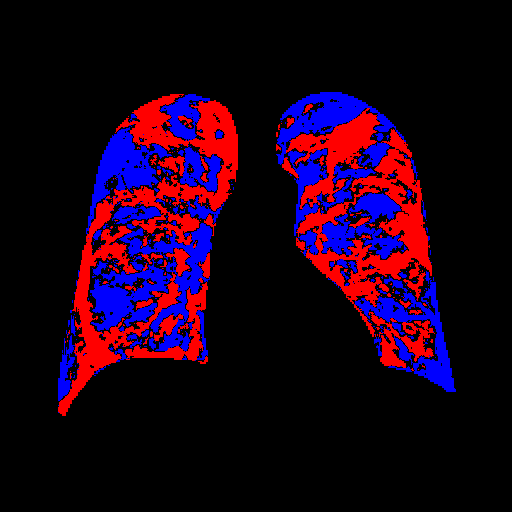

4.1 Qualitative Evaluation of Healthy Counterpart Generation

Example images from the disease COVID-19 Radiography Database and their generative healthy counterparts are given in figure 2. The images on the far left are instances of the lung opacity class from the real images in the dataset. The images in the middle column are examples of the generated healthy counterfactuals obtained via latent space diffusion, with RadBERT-guided textual-conditioning via a conditional prompt “normal chest x-ray”. A total of 75 diffusion inference steps are used with image conditioning strength=0.85 and guidance scale=7.5. (The former indicates the level of constraint on changes to the original input image and the latter is the weight given to the textual encoder conditioning in the generation of the image, ranging over [0,1] and [0,9], respectively).

Side-by-side inspection of the generated healthy counterfactuals (as per fig. 2) suggests that, as required, only minimal perturbation is made to the original image with respect to healthy pixels -i.e. localized image sites without structural medical defects. (In the top row, the medical structural defect in the original image is due to a lung opacity, and characterized via a relatively complex interaction between the imaging modality and subject manifesting as ‘gaps’ in the corresponding portions of the lung scan). The healthy/non-healthy discrepancy maps in all of these cases are obtained via masked subtraction of the original image from the generated image (the ground truth segmentation masks correspond to the broad area of interest –i.e. the complete lung). The generated healthy tissue is thus a subset of the mask and is shown in the final column of fig. 2 for the respective cases.

In the context of a VANT-GAN[20]-based approach, this highlighted material constitutes the diagnostic counterfactual visual attribution, i.e. the selection of material relevant to the diagnosis of the unhealthy condition. Healthy counterfactual generation was performed for the complete datasets in the three unhealthy classes, i.e Lung opacity, Viral Pneumonia and COVID, examples of which are given in fig. 3 for the three classes (all of the generated healthy counterfactuals from this experiment can be found on https://huggingface.co/ammaradeel/diffusionVA). Visual inspection indicates that the generated counterfactuals are, in general, visually plausible with minimal perturbation made to the unhealthy image overall. Moreover, the healthy counterpart generation does not appear to unnecessarily affect aspects of the images unrelated to the medical condition, the model selectively making changes to the unhealthy regions in a structurally plausible manner, e.g. generating missing portions of the lung without generating extraneous lung material where it would be expected to normally exist (e.g. in the abdominal cavity).